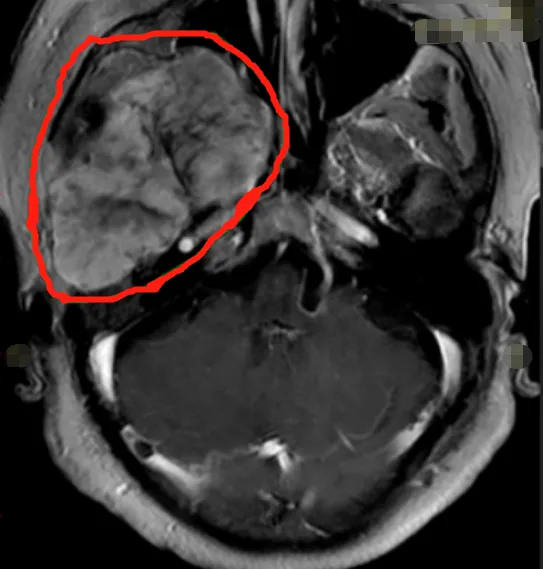

然而仅在部分切除手术的二年,赵先生就在复查检查种发现了脑膜瘤复发的情况,手术风险依旧存在,医生建议赵先生进行伽马刀治疗。3年伽马刀治疗非但没有如预期的控制肿瘤生长的效果,反而让赵先生的脑膜瘤继续恶化,MRI影像显示大脑镰前段基本均受累,并有大脑镰右侧肿瘤生长,矢状窦被累及,左侧额部凸面硬脑膜多处肿瘤生长。